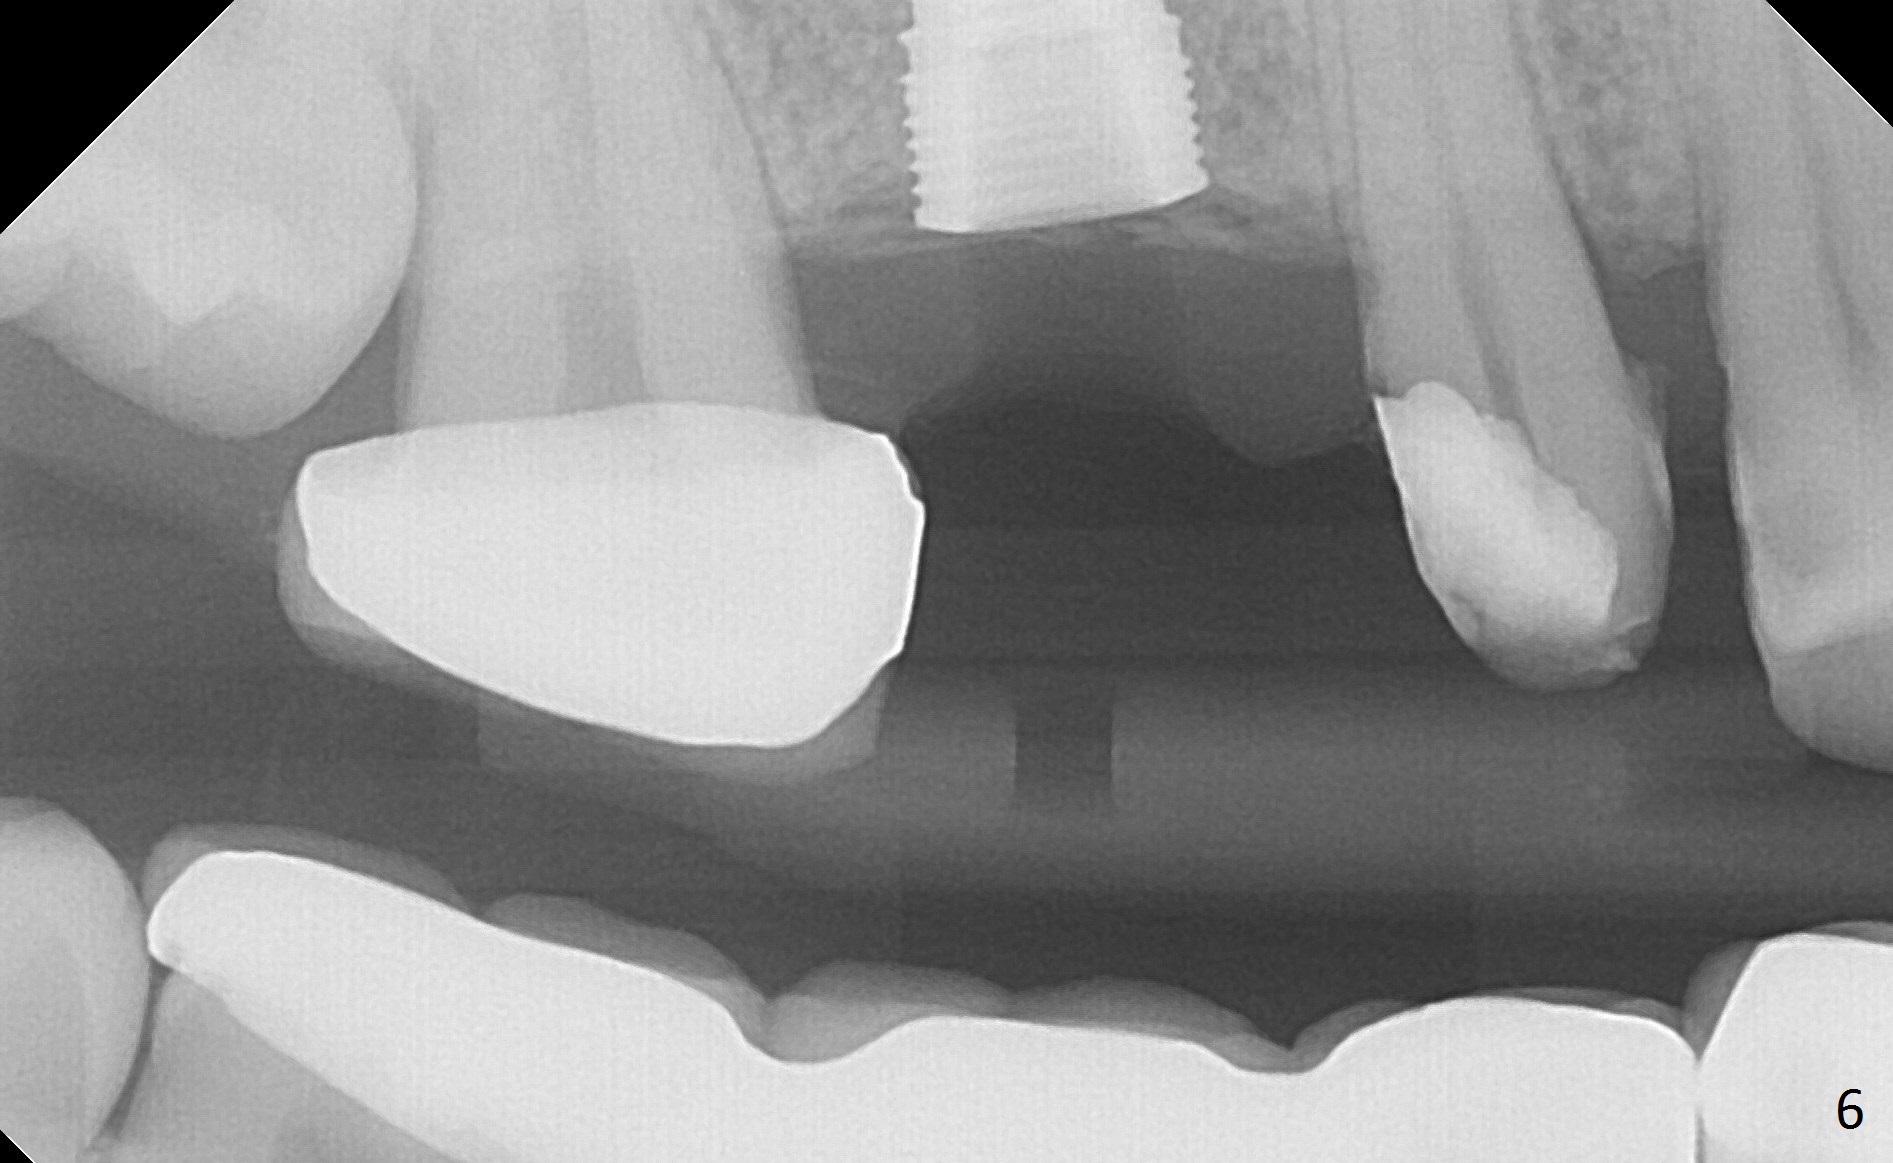

When the bridge is partially removed, the tooth #4 is found to have extensive caries. IRM is placed following carious removal (Fig.1). Magic Split testing shows that the bone density is high (flapless). Osteotomy is initiated by 1.6 mm drill, but the handle of the drill needs to shift mesial (Fig.1 red arrow). When the latter is done, the whole drill (2 mm) needs to move distal (Fig.2 double red arrows). When a 4.5x14 mm drill finishes the osteotomy, it is in the middle of the edentulous space (Fig.3). After use of 5 mm tap, a 5.3x14 mm implant cannot reach the depth (Fig.4,5). Following increase in osteotomy depth from 16 to 18 mm (gingival margin) until 5 mm drill in diameter, the implant placement level is more ideal (Fig.6,7, slightly subcrestal) with insertion torque maintaining at >55 Ncm. The sinus floor (Fig.4 arrowheads) may be penetrated when the osteotomy depth increases (Fig.7 *), but the sinus membrane remains intact.

In brief, osteotomy depth using flapless approach should be 4 mm more than the intended implant length (2 mm for gingival thickness and 2 mm for complete implant seating).